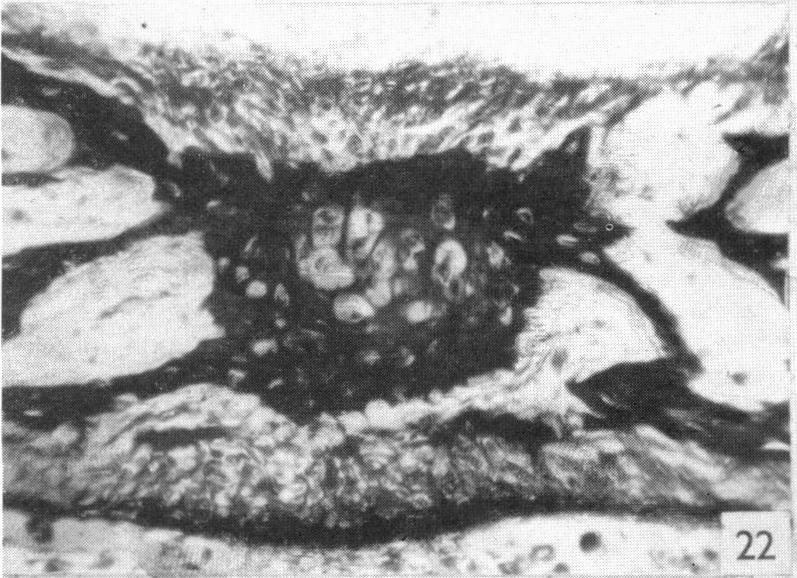

The structure and development of cranial and facial sutures.

PRITCHARD J J, SCOTT J H, GIRGIS F G

J Anat. 1956 Jan;90(1):73-86.